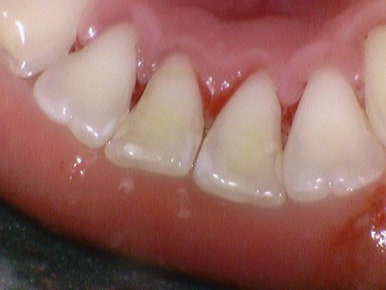

스케일링,잇몸치료, 앞니 크라운2개 전후

이렇게 스케일링을 하고 나면 치석이 없어지면서 치아가 빈것처럼 느껴질 수도 있고

부어있던 잇몸부분은 피가 나기도 하는데요

빈 부분이 생길지라도 없어야 하는 쓰레기(?)는 처리해야 하는 거니 스케일링은 해야겠죠.

또한 치아를 덮고있던 치석이 없어지면서 시린 느낌이 있을 수도 있으나, 없애야 하는 치석은 없애야합니다[! 단호]

치석이 쌓이면 심각한 입냄새도 유발하게 되므로 구취예방을 위해서도 제거하는 것이 좋습니다.